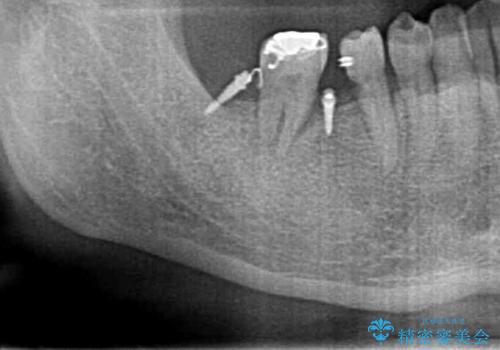

- 右下の親知らずが咬むと痛いとのことでした。

親知らずを抜いて、倒れこんでいる手前の歯を矯正治療で移動させ、ブリッジにしました。

矯正治療をしなければ、倒れこんでいる影響で手前の奥歯も含めて歯周病で悪化してしまうため、しっかり起こして治療をしました。

60代でしたが、歯もしっかり動いてブリッジを入れることができました。